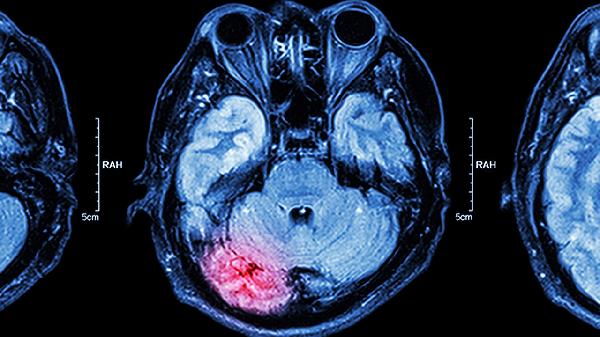

丹参、川芎等活血化瘀成分有助于促进脑部微循环,对血管性头痛、脑供血不足引发的头昏沉感有一定调节作用。此类情况常见于颈椎病患者或中老年人群。